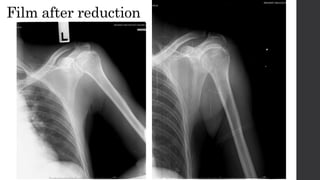

• Film after reduction

Film after reduction